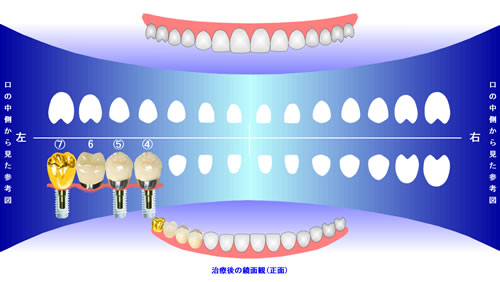

補綴説明シミュレーションも簡単

ビジュアルな写真画像での補綴説明シミュレーションが簡単にできます!

補綴説明

これはサンプルの説明文です。各箇所に短めの説明文を入れます。これはサンプルの説明文です。各箇所に短めの説明文を入れます。